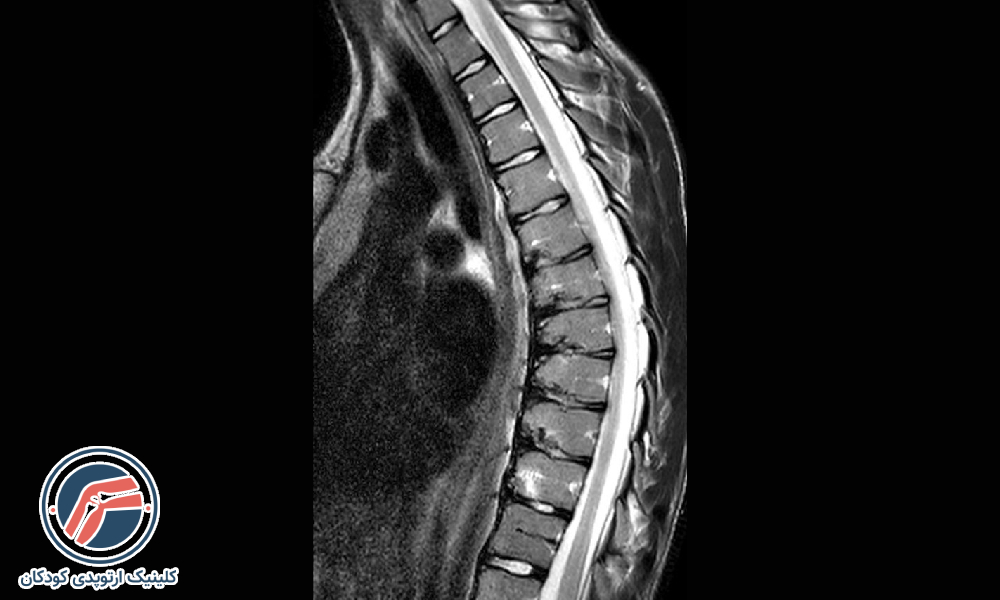

- تصویربرداری: تصویربرداری به مشخصشدن دقیقتر انحنا و میزان قوس کمر کمک میکند. معمولاً پزشکان کودکانی که دارای کیفوز خفیف هستند را بهدقت تحتنظر میگیرند و در دورههای ۶ ماهه از ستون فقرات آنها بهوسیله اشعهایکس یا MRI تصویربرداری میکنند. در بزرگسالان علاوه بر تصویربرداری ممکن است که به آزمایش خون و آزمایش تراکم استخوان نیز برای تشخیص دقیقتر نیاز باشد.